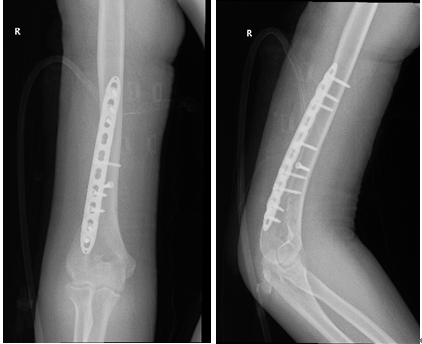

X光可见小强的右肱骨下段出现骨折。

在完善术前准备后,厦门市中医院骨伤科何发胜主任、刘胜主任及唐聪医师团队为小强做了

骨折切开复位钢板螺钉固定手术。小强手术后需休养康复至少3个月,学业肯定得受影响了。

小强术后的X光片,可以看见用于固定的钢板。